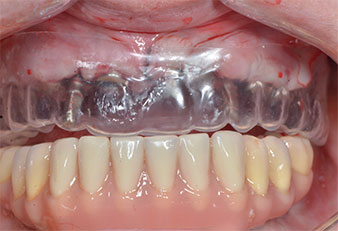

Tres años después, llegó el momento de colocar una prótesis del mismo tipo en el maxilar superior. Basándose en una planificación mediante tomografía computarizada de haz cónico (CBCT, por sus siglas en inglés), se evitó la necesidad de realizar una elevación del seno utilizando implantes cortos, mientras que una plantilla quirúrgica sirvió para transferir las posiciones planificadas al borde alveolar (figuras 1 y 2).

Debido al hueso relativamente duro (D2) existente en el sector anterior, los sitios de los implantes largos de 10 mm de las posiciones 11 y 21 se finalizaron con una fresa rotatoria de 4 mm de diámetro, en combinación con un contra-ángulo quirúrgico WS-75 L de W&H, el motor de implantes Implantmed de W&H y el módulo opcional Osstell ISQ de W&H. En cambio, debido a la existencia de hueso blando, los sitios posteriores se prepararon hasta un diámetro final de 3 mm utilizando el inserto Piezomed I3P. Por último, los implantes se colocaron a nivel crestal para su osteointegración durante tres meses (figuras 6-10). La prótesis existente se mantuvo sobre cuatro implantes provisionales (figura 8).